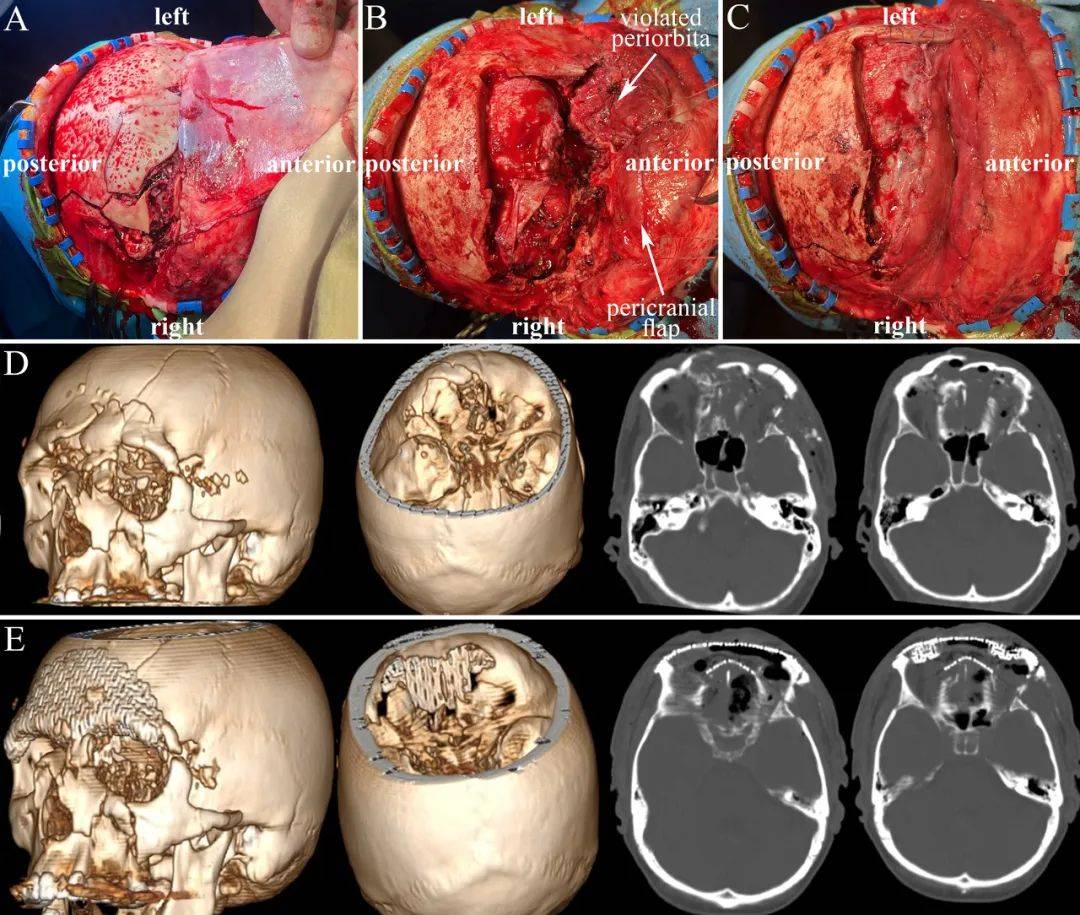

颅脑外伤后遗症有哪些

重型颅脑外伤常遗留的并发症和后遗症如下1并发症脑脊液瘘,大多数脑脊液瘘在一周左右会自行闭合,如超过两周需手术处理颈内动脉海绵窦瘘,指颅底骨折刺伤颈内动脉血管,患者出现波动性凸眼颅内杂音口鼻流血症状,需做介入和海绵窦手...